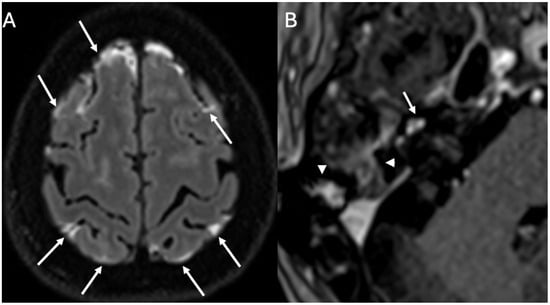

3.1. Otomastoiditis

3.1.1. Imaging

| Otomastoiditis and Otogenic Meningitis | Saat et al., 2015 [17]; Rubini et al., 2024 [18]; Vazquez et al., 2003 [19]; Bruschini et al., 2017 [20]; Barry et al., 2019 [21] | Retrospective studies, imaging reviews, and case reports | HRCT and MRI identify middle ear/mastoid infection and intracranial spread; meningitis occurs in up to 35–46% of untreated cases. |